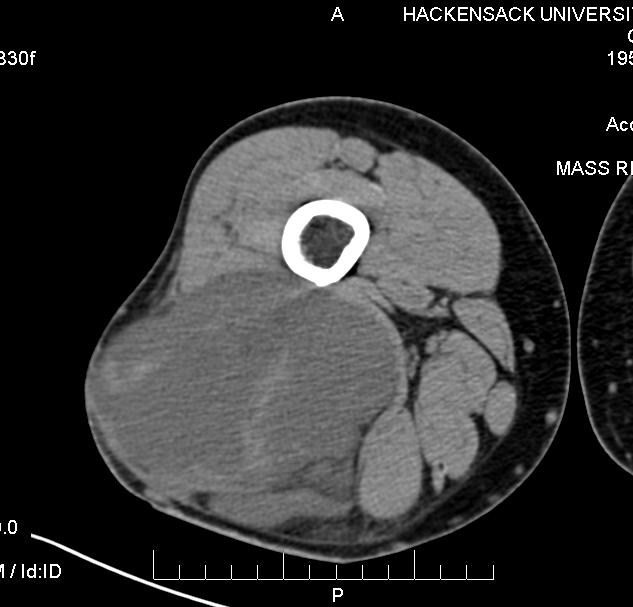

CT

• Inhomogeneous masses of low density on CT with enhancing areas (Fig. 1)

Patterns based on amount and distribution of fat:

1. solid – attenuation > + 20 HU

2. mixed – areas of < -20 HU and areas of > + 20 HU

3. pseudocystic – homogenous density between – 20 and + 20 HU

CT findings favoring a liposarcoma from a lipoma include

• Poor definition of adjacent structures